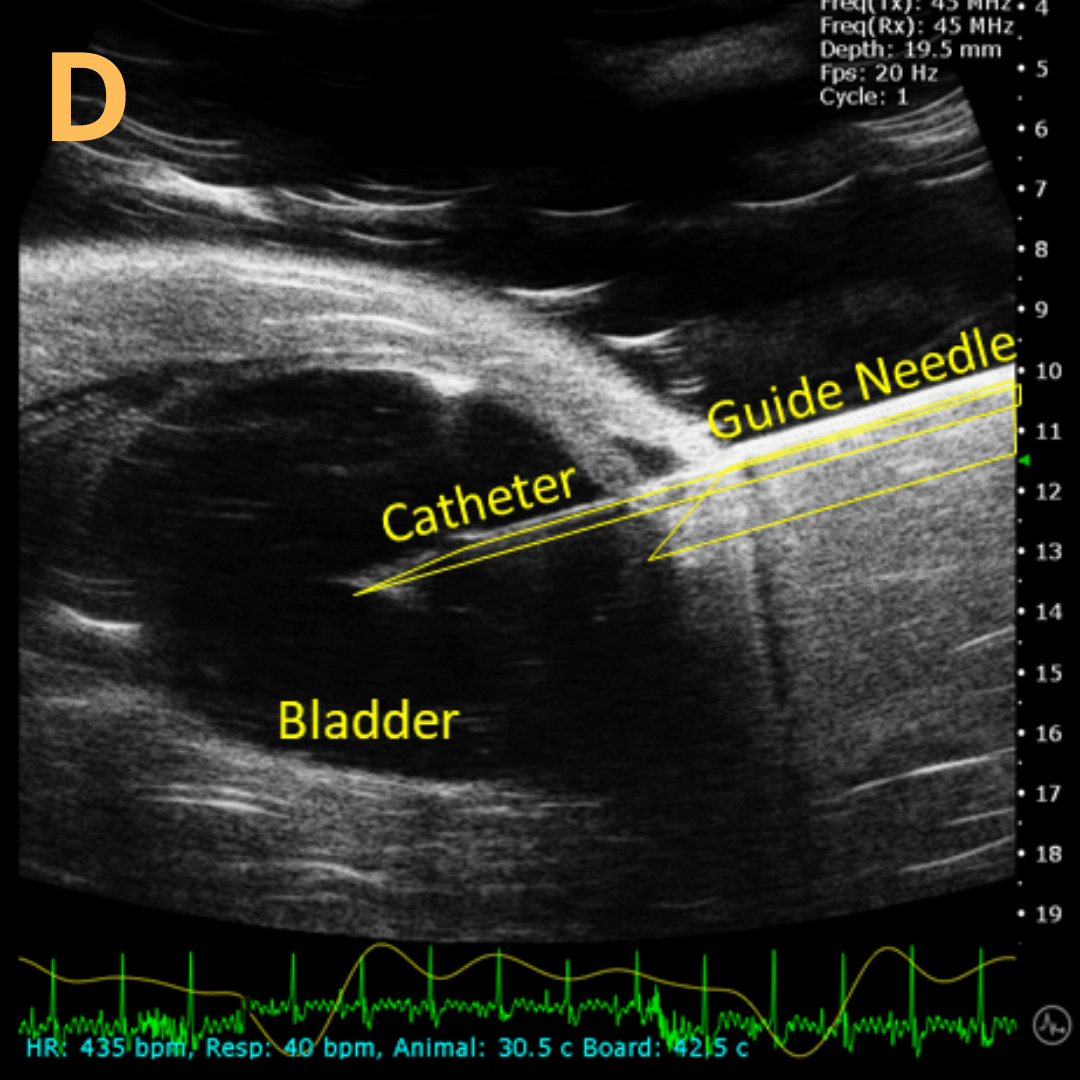

Ultrasound-Guided Bladder Catheterization

This is A) a B-mode video showing insertion of a thin-needle catheter via a larger-sized guide needle with B) the landmarks noted. C) is another example of this technique with D) the landmarks noted. E) Removal of catheter needle with F) the landmarks noted. Verification of successful injection via catheter is shown in G – H with G) showing the bladder before injection and H) showing after successful injection. Imaging on a wildtype C57B6J mouse model – acquired images are from Stephen Zderic’s lab at the Children’s Hospital of Philadelphia.

An in-plane introducer (guide) needle was used to puncture through the skin of the animal, while a thin needle catheter was fed through the introducer needle and used to puncture through the bladder wall. Using the catheter prevents potential leakage or complete collapse of bladder.